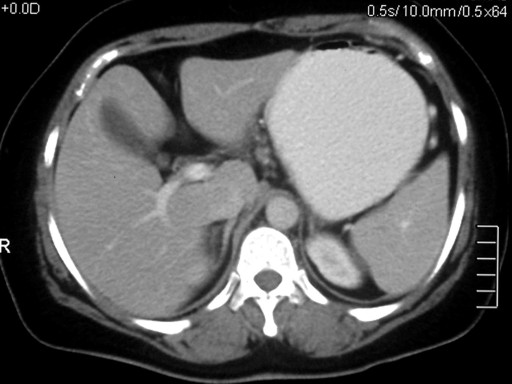

A 40-year-old female presented with abdominal pain of three months duration. The pain was located in the upper abdomen with radiation to the back. There were no exacerbating factors and the pain subsided with the ingestion of oral opioids. The patient also complained of weight and appetite loss. There was no history of alcohol ingestion. Her laboratory studies revealed an elevated erythrocyte sedimentation rate (46 mm in first hour; reference range: 0-20 mm) and were otherwise unremarkable. Serum amylase was 320 IU/L (reference range: 0-160 IU/L). A chest radiograph did not reveal any abnormality. Ultrasound of the abdomen did not reveal any abnormality and the pancreas was obscured by the bowel gases. Contrast-enhanced computerized tomography (CECT) of the abdomen demonstrated the bulky head and body of the pancreas with heterogeneous areas of non-enhancement suggestive of necrosis and peripancreatic fat stranding (Figure 1). The splenic vein was not visualized which was suggestive of thrombosis. The CECT findings were suggestive of focal pancreatitis involving the head and body of the pancreas with splenic vein thrombosis. As the patient had no history of severe pain which required admission, had ongoing chronic pain with loss of weight and appetite and a bulky head and body of the pancreas, image-guided fine needle aspiration was carried out to exclude a pancreatic malignancy. The cytological examination of the CT-guided fine needle aspiration revealed caseous necrosis. No acid-fast bacilli could be demonstrated. The Mantoux test was negative. However, a culture of the aspirated material demonstrated the growth of Mycobacterium tuberculosis. The patient was treated with anti-tubercular therapy for twelve months (four drugs for two months and two drugs for ten months). The patient improved with the therapy and was asymptomatic after completing two months of therapy. A repeat CECT of the abdomen performed after completion of the therapy revealed a normal pancreas with no focal lesions (Figure 2). The splenic vein was attenuated and collaterals were noted at perigastric, perisplenic and gastrohepatic locations (Figure 3). No varices were noted on upper gastrointestinal endoscopy. After four months of follow-up, the patient is asymptomatic.

Figure 2. Contrast-enhanced computerized tomography (CECT) of the abdomen performed after completion of the therapy showing a normal pancreas with no focal lesion. |